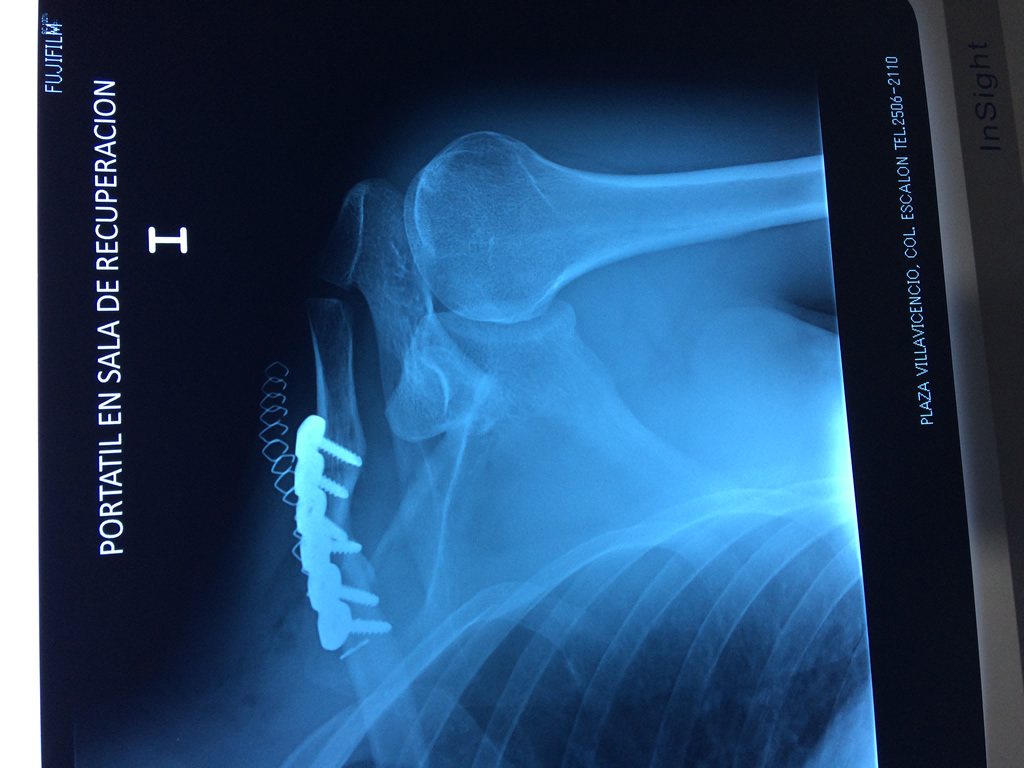

Cirugías de Hombros - Clavícula